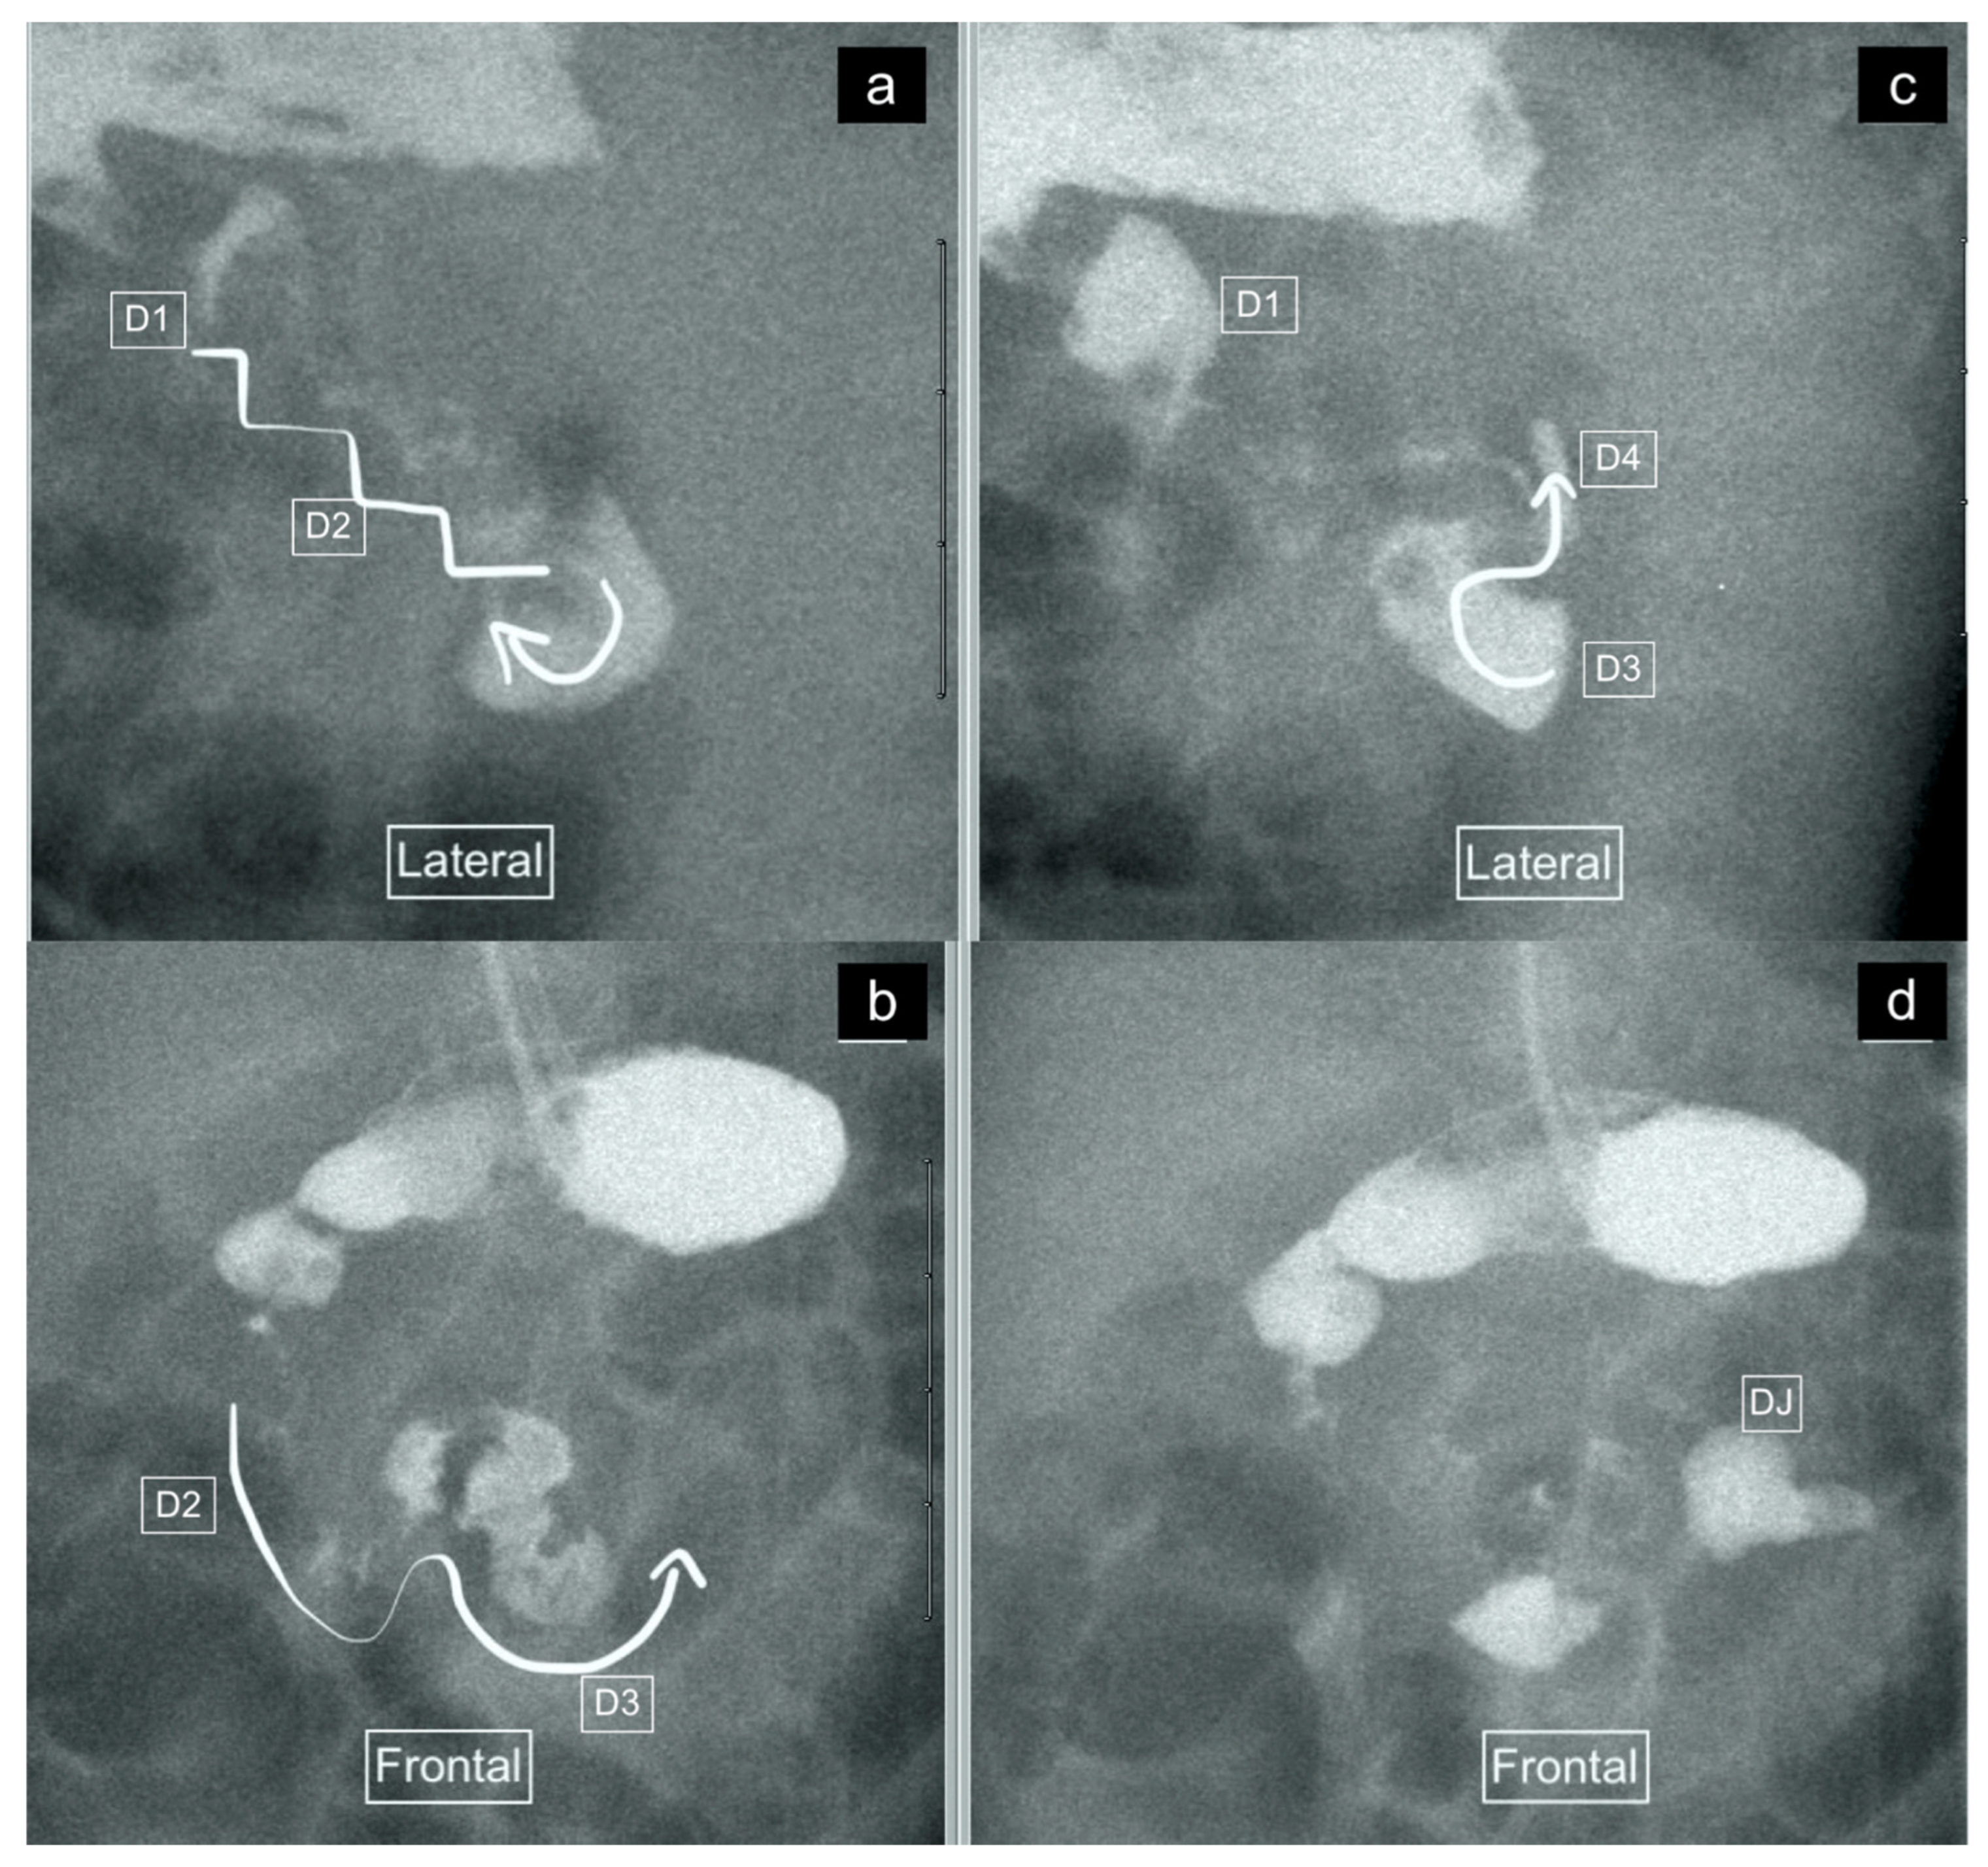

Figure 3.

(a–d): Representative images captured during an UGIS in a 49-day-old boy demonstrating duodenum redundum on the frontal and lateral views, with the order of images representing the order that the images were captured through multiple repositioning maneuvers. (a) Lateral view demonstrating the descending staircase sign oriented posteriorly from D1 and involving D2. (b) Frontal view demonstrating the W-loop configuration of duodenum redundum made up here by D2 and D3. (c) Repositioning in the lateral view demonstrates the posterior position of D3 inferiorly and that the ascending D4 remains posterior. (d) Return to the frontal position now demonstrates the contrast outlining the duodeno-jejunal flexure (DJ) just slightly inferior to D1 and to the left of the spine—considered within the normal range allowing for patient positioning.

Figure 4.

(a,b): Representative images captured during an UGIS in a 2-month-old boy demonstrating duodenum redundum on the lateral and frontal views. (a) Lateral view demonstrates a descending staircase configuration of D1 and D2 oriented posteriorly, after which the duodenum remains (D3) and ascends (D4) in the retroperitoneal position, leading towards the duodeno-jejunal junction (not shown here). (b) Frontal view demonstrates redundancy of the duodenal loop which, instead of having a C-loop configuration, has a W-loop configuration, made up of D2, D3 and D4 (white line) and a normal position of the duodeno-jejunal flexure (DJ).